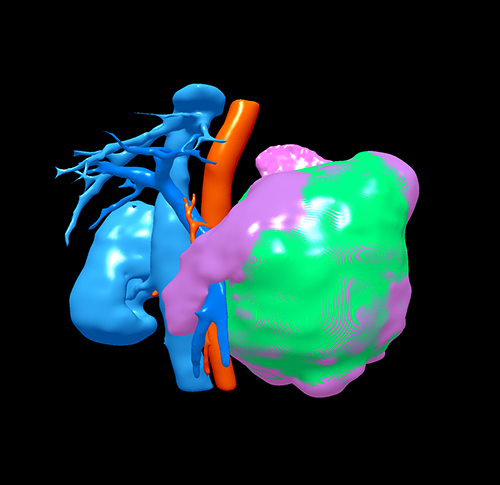

胰体尾囊腺瘤---腹腔镜胰体尾切除